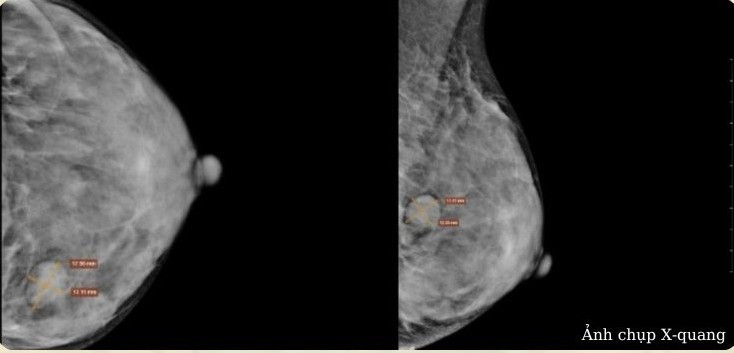

Tại viện, bệnh nhân được khám lâm sàng, siêu âm và chụp X-quang tuyến vú, kết quả đều cho thấy tổn thương hướng tới nhân xơ tuyến vú lành tính, phân loại BIRADS 3.

| Hình ảnh chụp X-quang của bệnh nhân phát hiện khối U xơ. Ảnh BVCC |